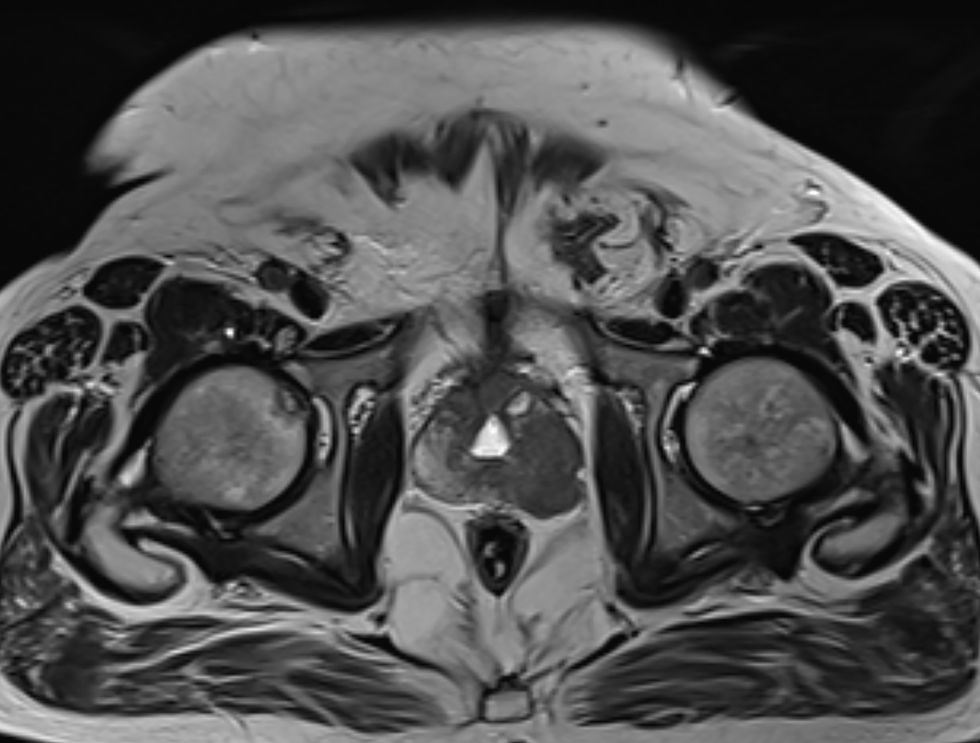

Perhaps most compelling was the case of a 63-year-old gentleman whose cancer had metastasised to his liver.

Following six treatment cycles, all 14 cancerous lesions in his liver had completely disappeared - a result Prof de Bono described as unprecedented for this traditionally "immune-cold" malignancy.